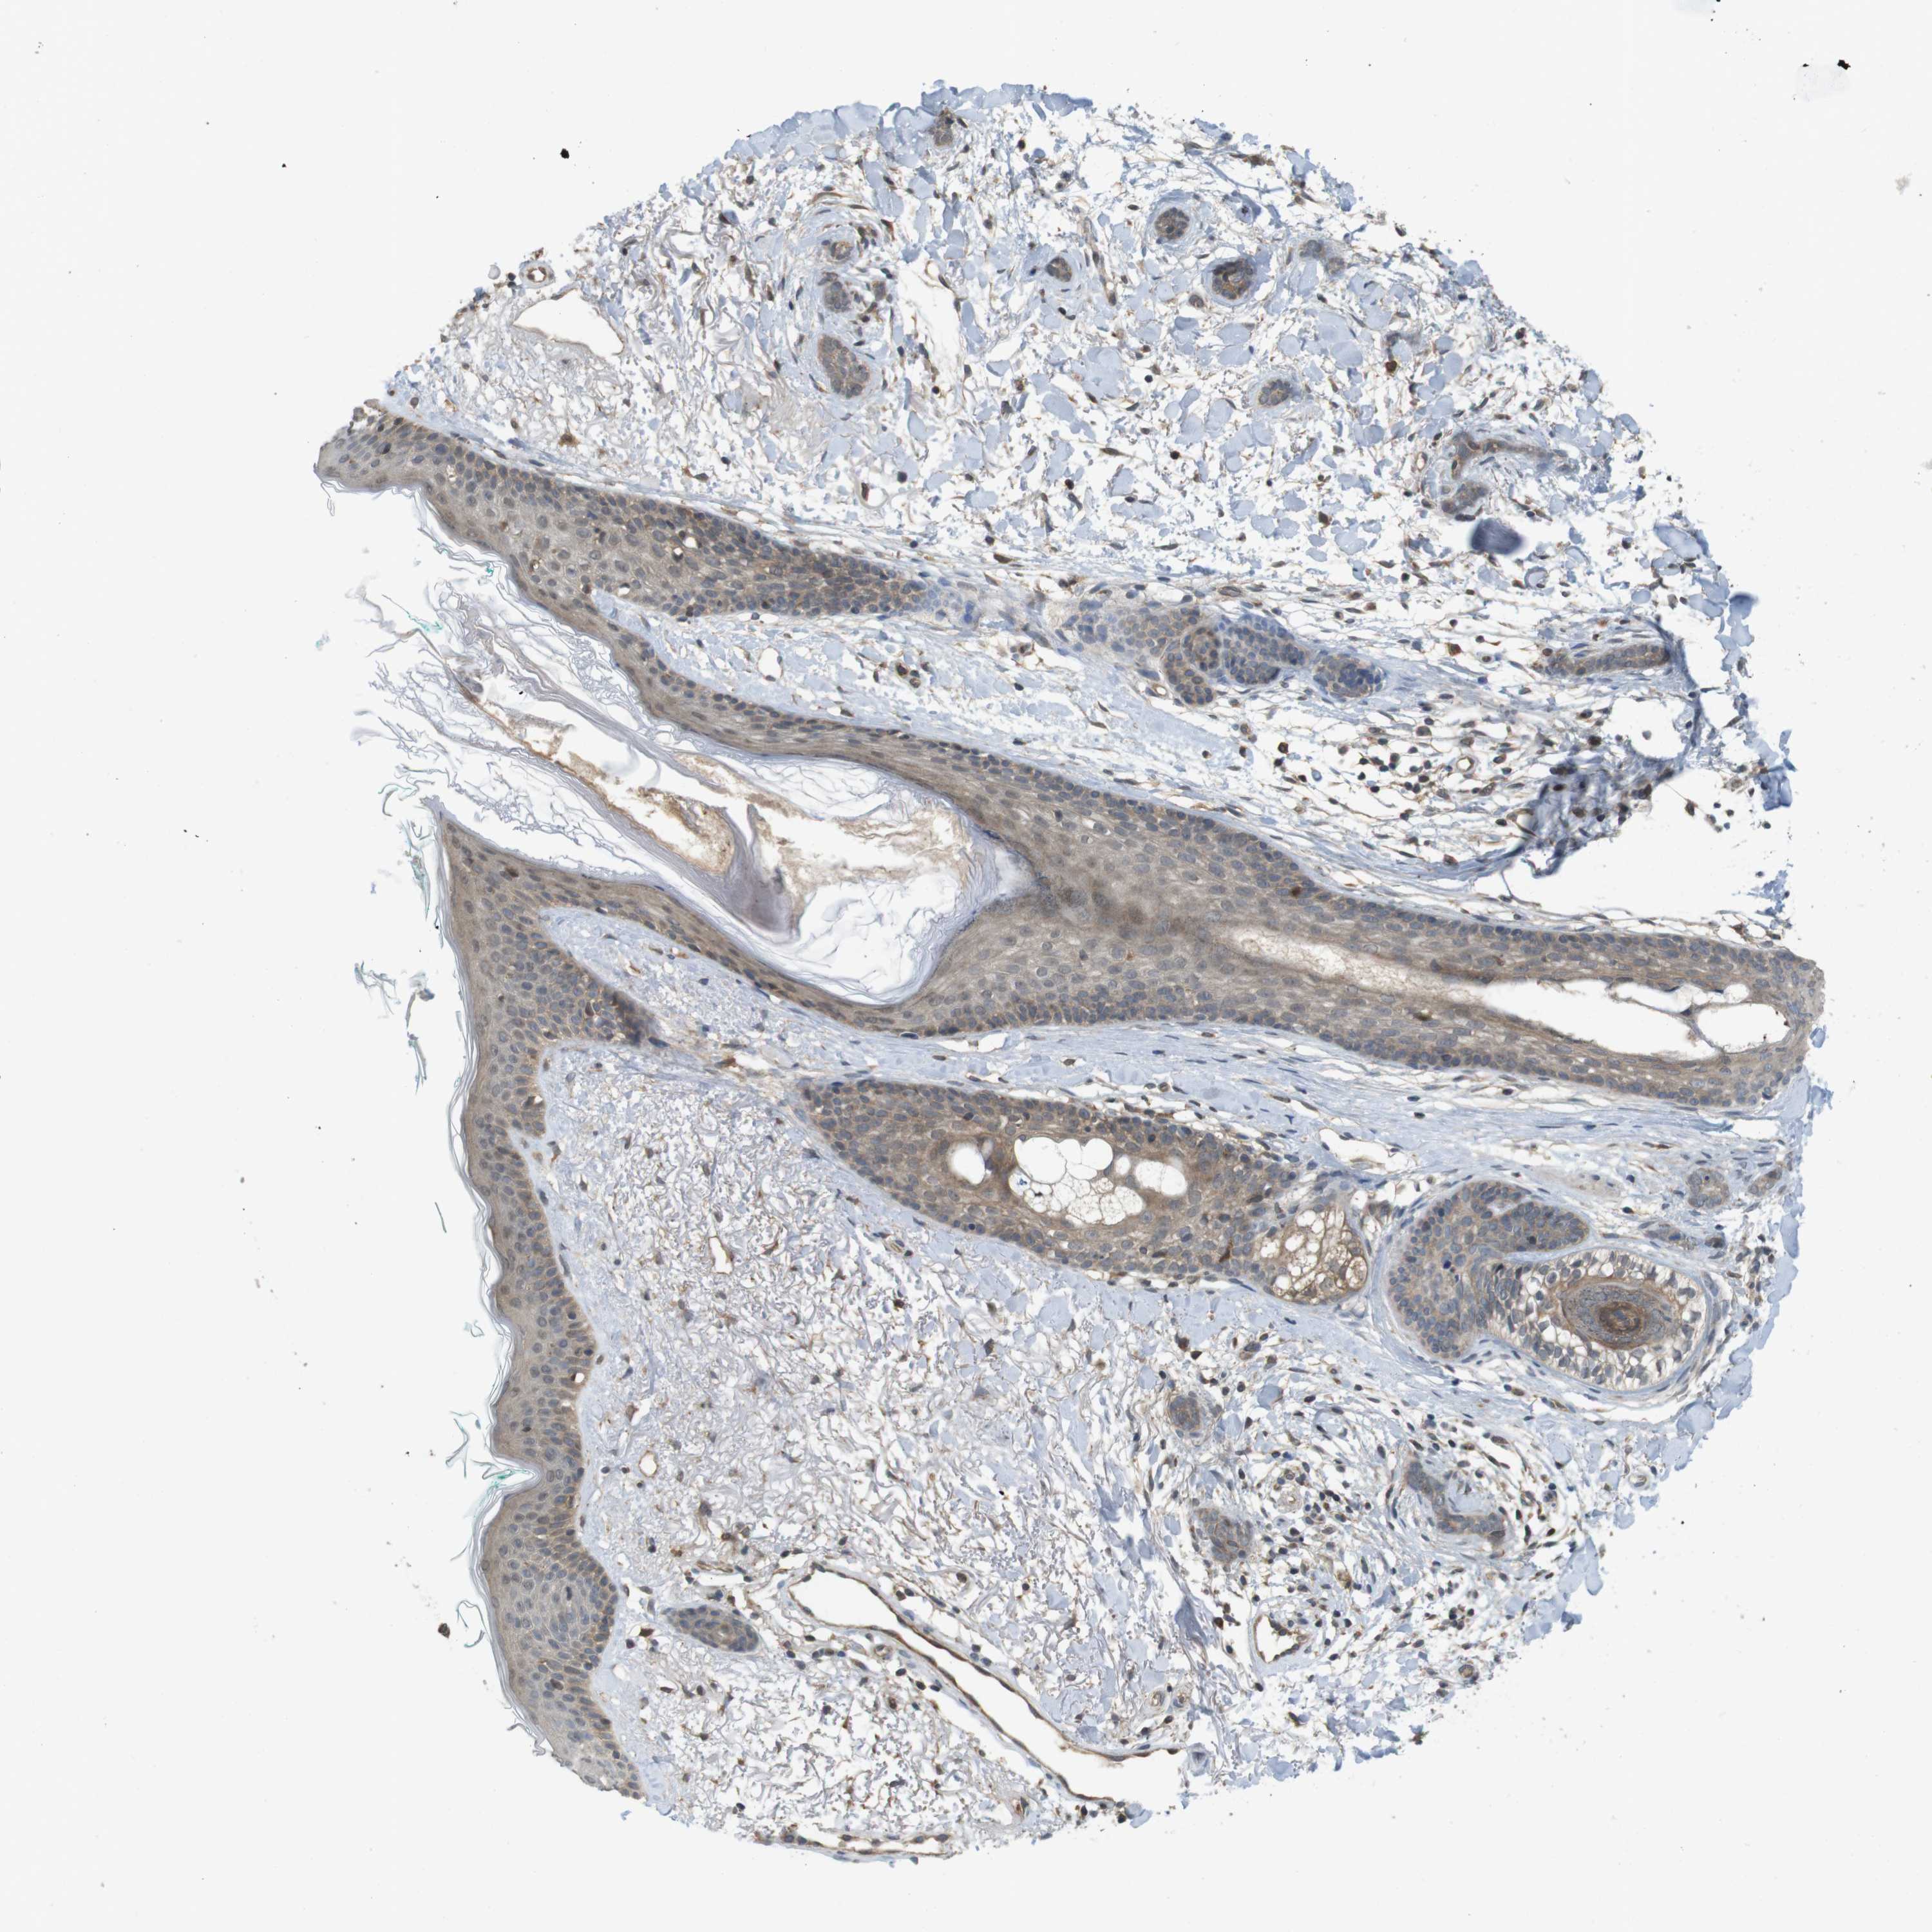

SKIN CANCER

Basal cell and squamous cell cancer